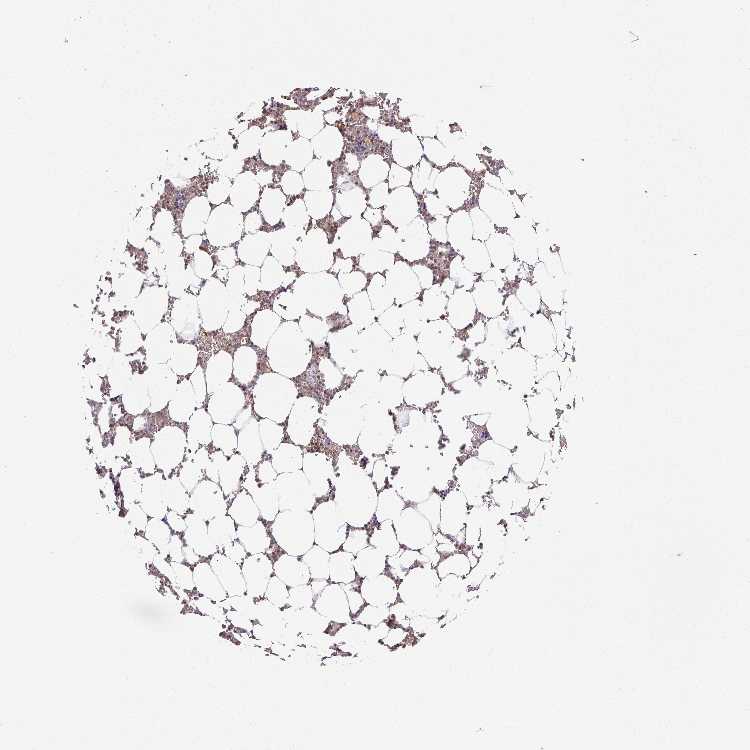

BONE MARROW - Antibody stainingi

Antibody staining in the annotated cell types in the current human tissue is reported as not detected, low, medium, or high, based on conventional immunohistochemistry profiling in selected tissues. This score is based on the combination of the staining intensity and fraction of stained cells.

Each image is clickable and will lead to virtual microscopy that enables deeper exploration of all samples and also displays staining intensity scores, fraction scores and subcellular localization as well as patient and tissue information for each sample.

Antibody HPA034961Antibody HPA055634

Hematopoietic cells Not detectedLow